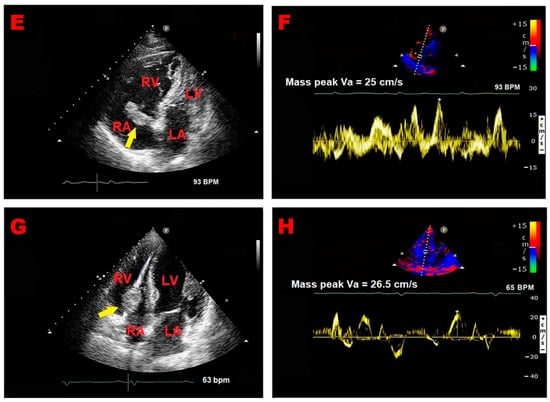

Representative examples of RA thrombus, myxoma, and vegetation assessed by TTE implemented with PW-TDI are illustrated in Figure 3A–F.

Figure 3.

Representative examples of RA thrombus, myxoma, and vegetation assessed by TTE implemented with PW-TDI. (A) Transthoracic echocardiography. Apical four-chamber view, showing large S-shaped RA thrombus (yellow arrow) entrapped in the Chiari network, prolapsing through the tricuspid valve into the right ventricle. (B) PW-TDI assessment of the thrombotic mass motility: the pattern of incoherent motion is typical of a pathological RA mass. (C) Transthoracic echocardiography. Apical four-chamber view, revealing RA atrial multilobulated, hypermobile, echogenic cauliflower mass attached to the tricuspid lateral annulus with a short stalk (yellow arrow), compatible with a pedunculated myxoma. (D) PW-TDI assessment of the RA myxoma motility: the mass motility is totally independent of the cardiac cycle. (E) Transthoracic echocardiography. Apical four-chamber view, demonstrating an echogenic mass attached to the fossa ovalis, extending into the RA (yellow arrow), compatible with RA myxoma. (F) Pattern of uncoordinated motion of RA myxoma assessed by PW-TDI. (G) Transthoracic echocardiography. Apical four-chamber view, highlighting large vegetation attached to the pacemaker lead in the right atrium (yellow arrow) of a patient with infective endocarditis. (H) Pattern of incoherent motion of RA vegetation on PW-TDI. LA, left atrium; LV, left ventricle; PW, pulsed wave; RA, right atrium; RV, right ventricle; TTE, transthoracic echocardiography; TDI, tissue Doppler imaging; Va, antegrade velocity. (C,D) are reproduced from the paper [24] (license number 5917070978039).